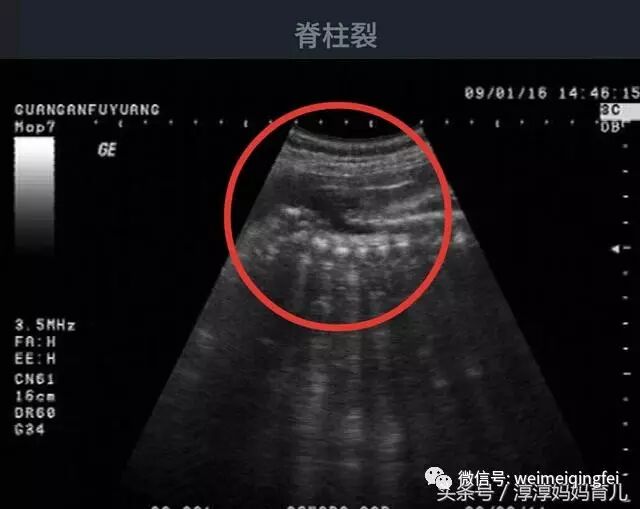

医生却说“你太大意了,不管是第几胎,你都得操心啊,孩子有重度脑积水伴有脊柱裂,即使生下来也不一定能存活,家属还是考虑一下引产吧。”这时候孕妇及其家属才意识到问题的严重性,在检查室就痛哭流涕,后悔没有重视检查。

脑积水:一般是指脑脊液过多地聚集于脑室系统内,致使脑室系统扩张和压力升高,在新生儿中该病的发生率约为2%。

侧脑室后角宽度>1.0cm,<1.5cm为轻度脑室扩张;侧脑室后角宽度>1.5cm为脑积水或明显脑室扩张,第三脑室和第四脑室也可增大,如果没有合并其他脑发育畸形称为孤立性脑积水。

一般来说,胎儿脑积水出生后的预后和其伴发其他畸形关系很密切,伴有其他畸形的胎儿围生期死亡率较高。

发现轻度脑积水医生是很难向孕妇及其家属提供产前咨询的,但是当发现向上面的孕妇的情况,重度脑积水并伴有其他胎儿畸形的一般是建议终止妊娠的。